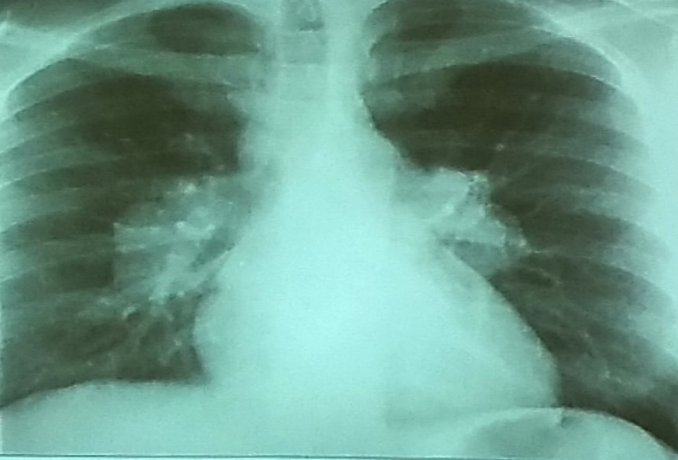

A 32 years old male presented with history of low grade fever, cough with sputum, sometimes blood stained. He has weight loss of 5 kg during this period. His chest X-Ray is shown ABOVE.

Describe the abnormality seen in the X-Ray?

- Cavitation and consolidation in the left upper lung

- bilateral Hilary lymphadenopathy

What is the likely diagnosis? Pulmonary TB

Mention 2 other investigations which you will advise?

- o Sputum culture and smear

- o IGRA

Mention 2 factors which increase the risk of this disease?

- HIV

- Chemotherapy

Mention 2 drugs used to treat this medical condition?

- o Rifampicin

- o INH (Isoniazid)